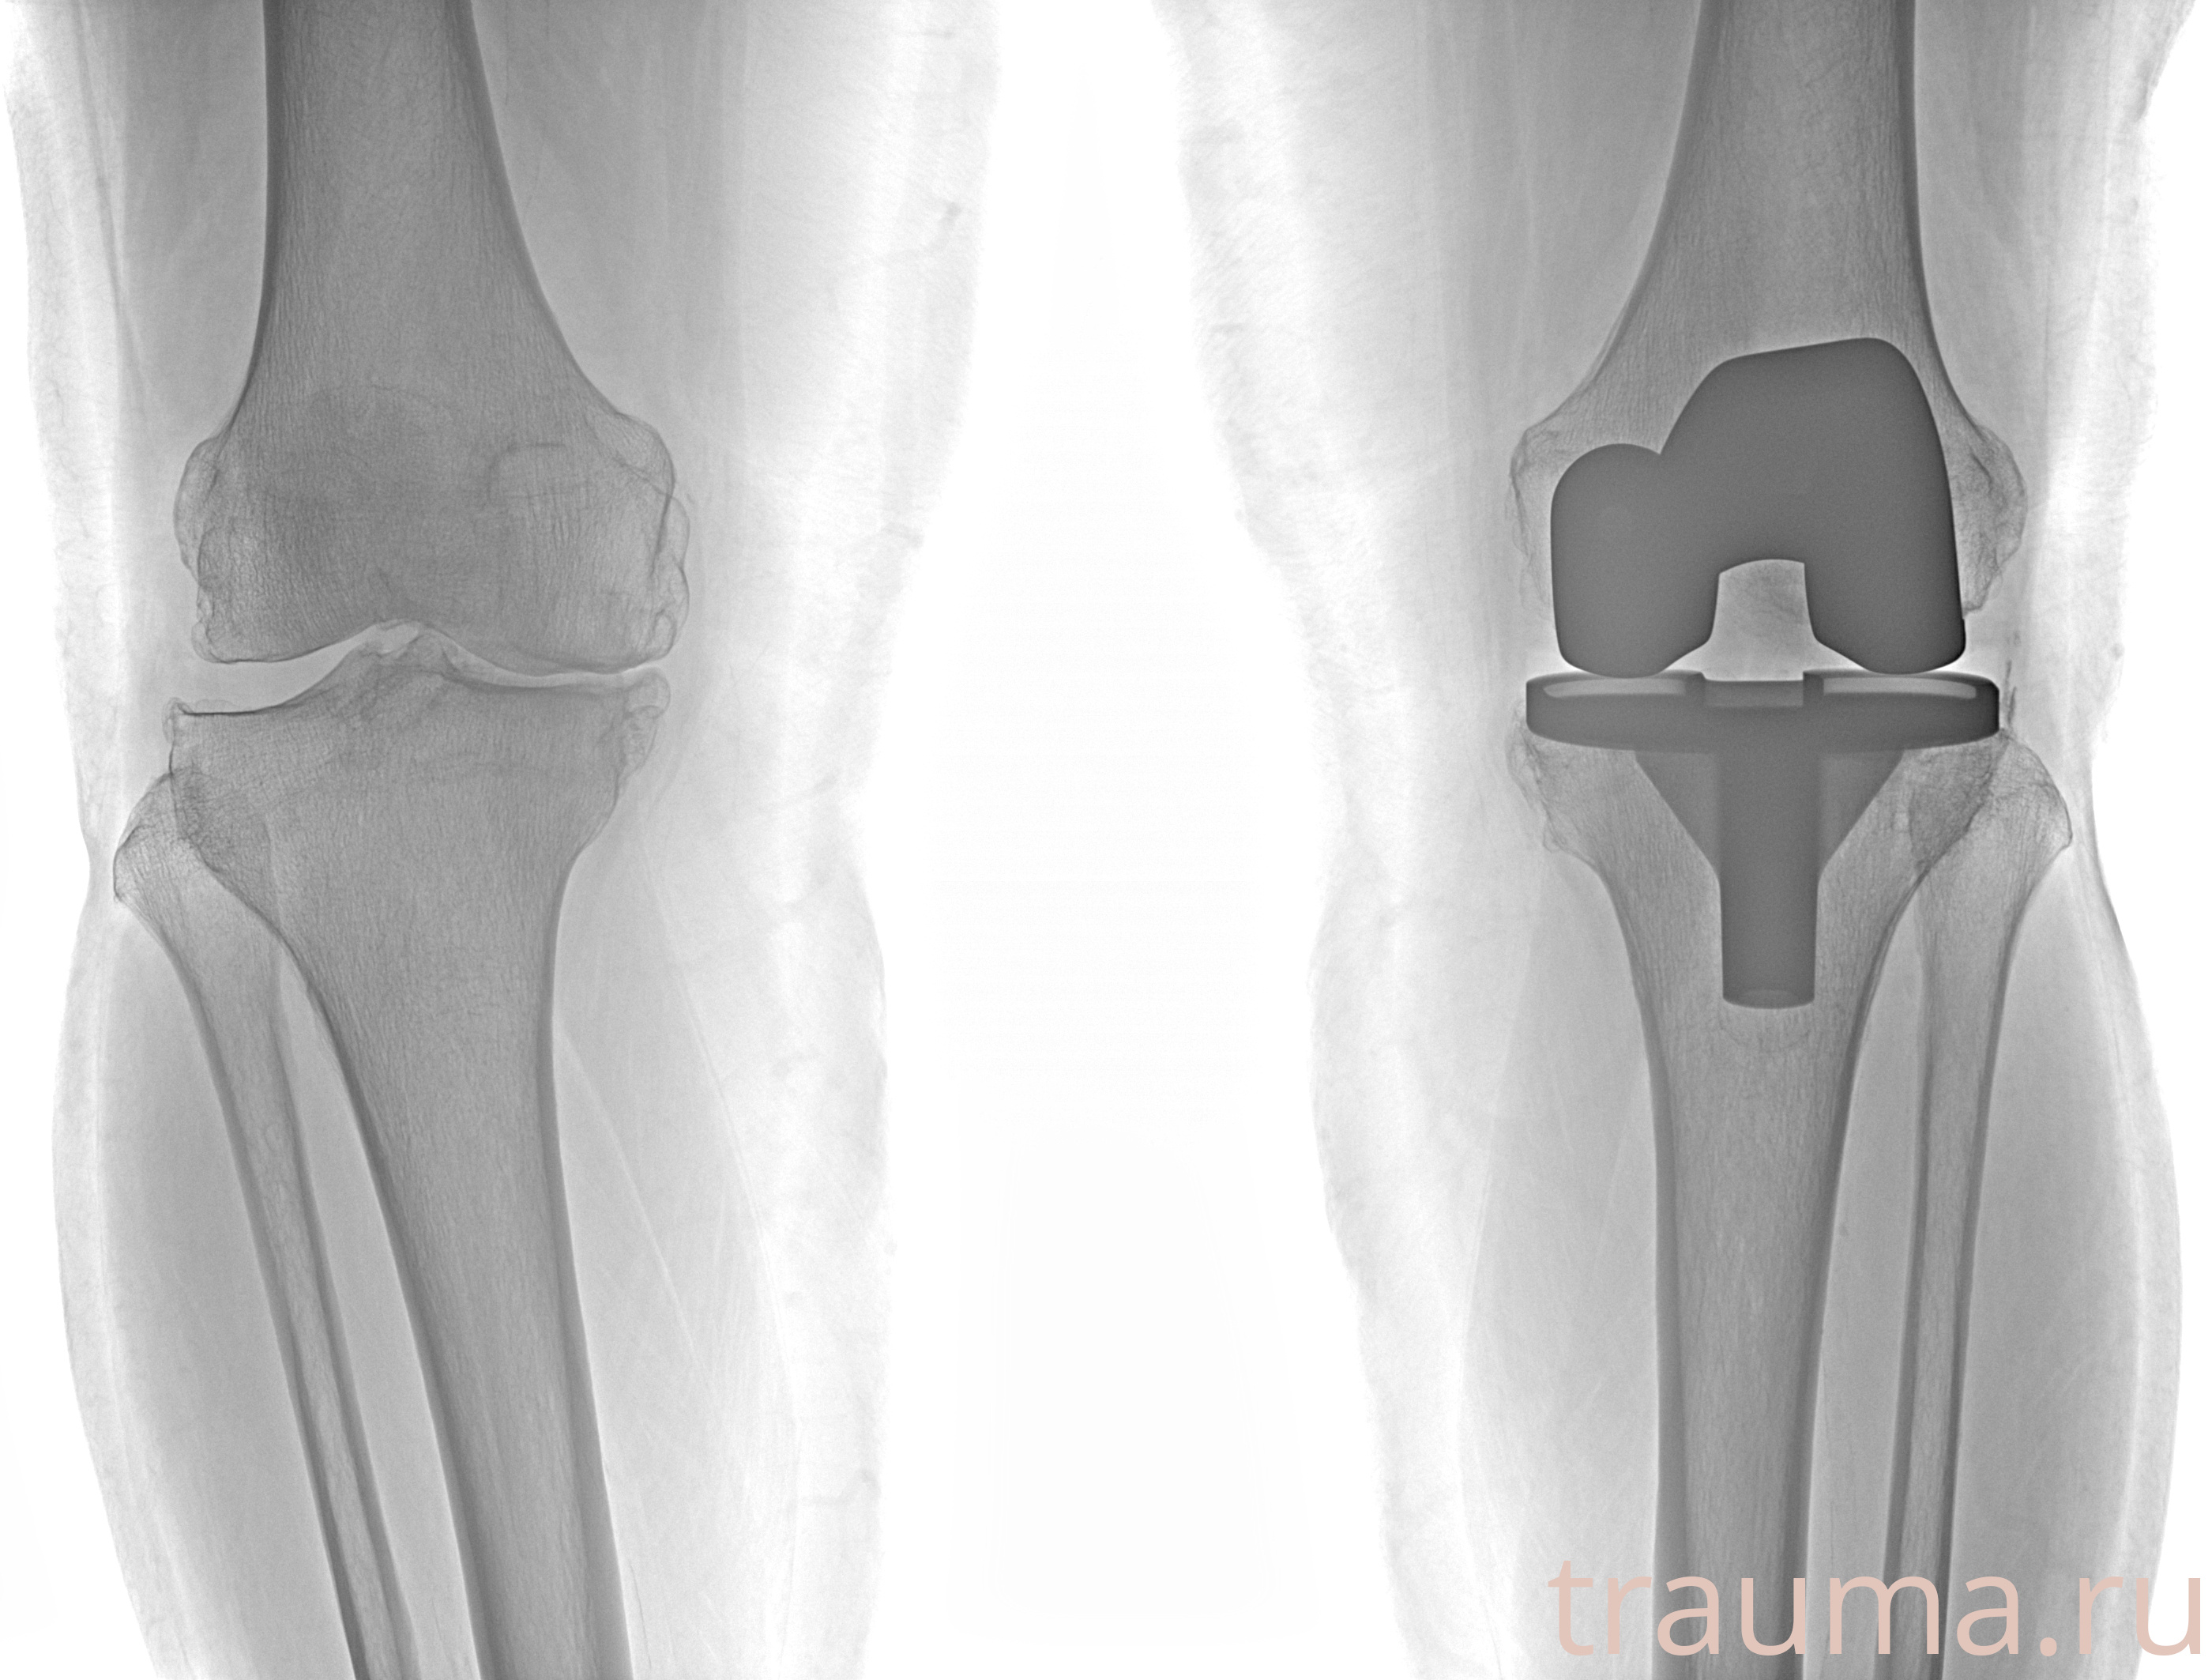

Рентгенограммы

Сравнить:

Яркость: 1   Контраст: 1   Инвертировать: 0 Увеличение: 1

Перетаскивайте мышь вверх/вниз для контраста, влево/право для яркости. Прокрутка колесом изменяет масштаб. Нажмите Сбросить для возврата к исходному изображению. При увеличении держите мышь в той области, которую хотите рассмотреть.